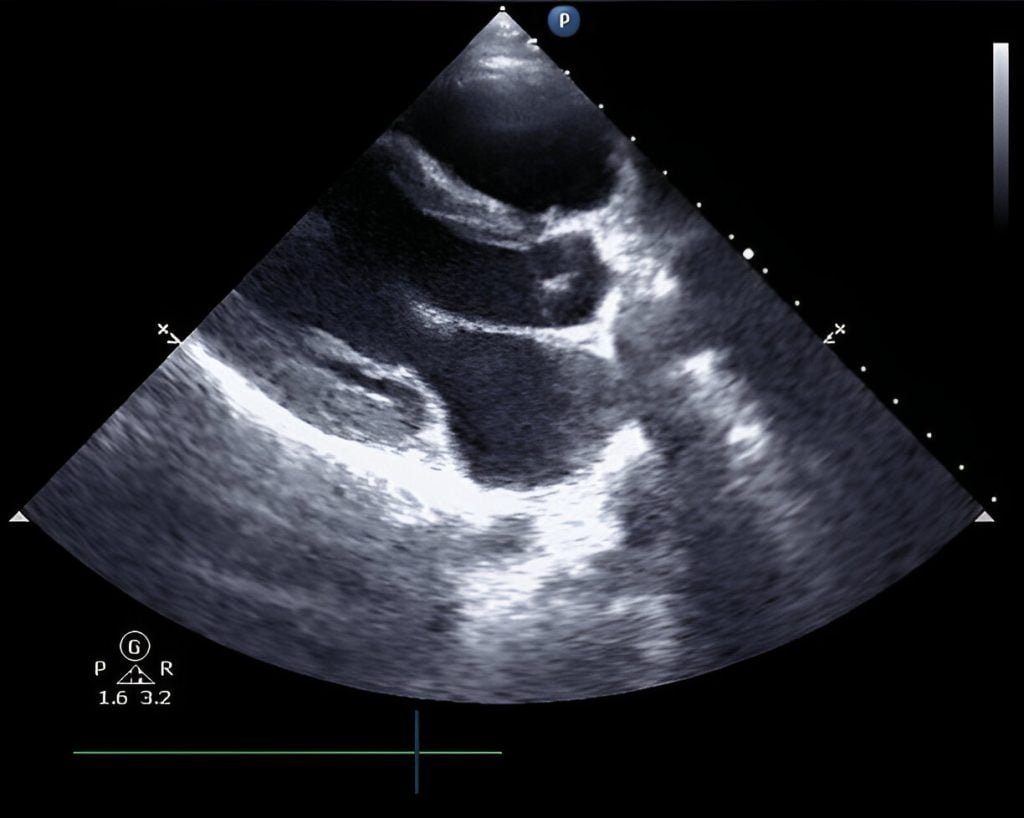

Non-invasive cardiology includes diagnostic tests like echocardiograms and stress tests that do not require surgical intervention.

echocardiogram scan